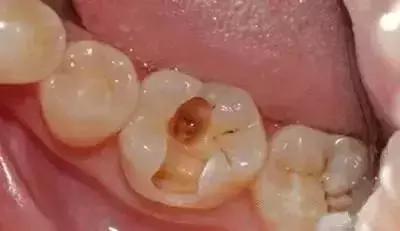

牙本质腐蚀,龋坏进一步加深,形成龋洞,牙齿冷热酸疼

窝沟龋已经向两侧扩散,窝洞形成。这种情况下,窝沟可以明显用肉眼看出来,大块的,不规则的黑洞。在牙齿还没有疼之前,赶紧去牙科,去除黑色龋坏部分,再用补牙材料填充,及时止损,保护牙齿。